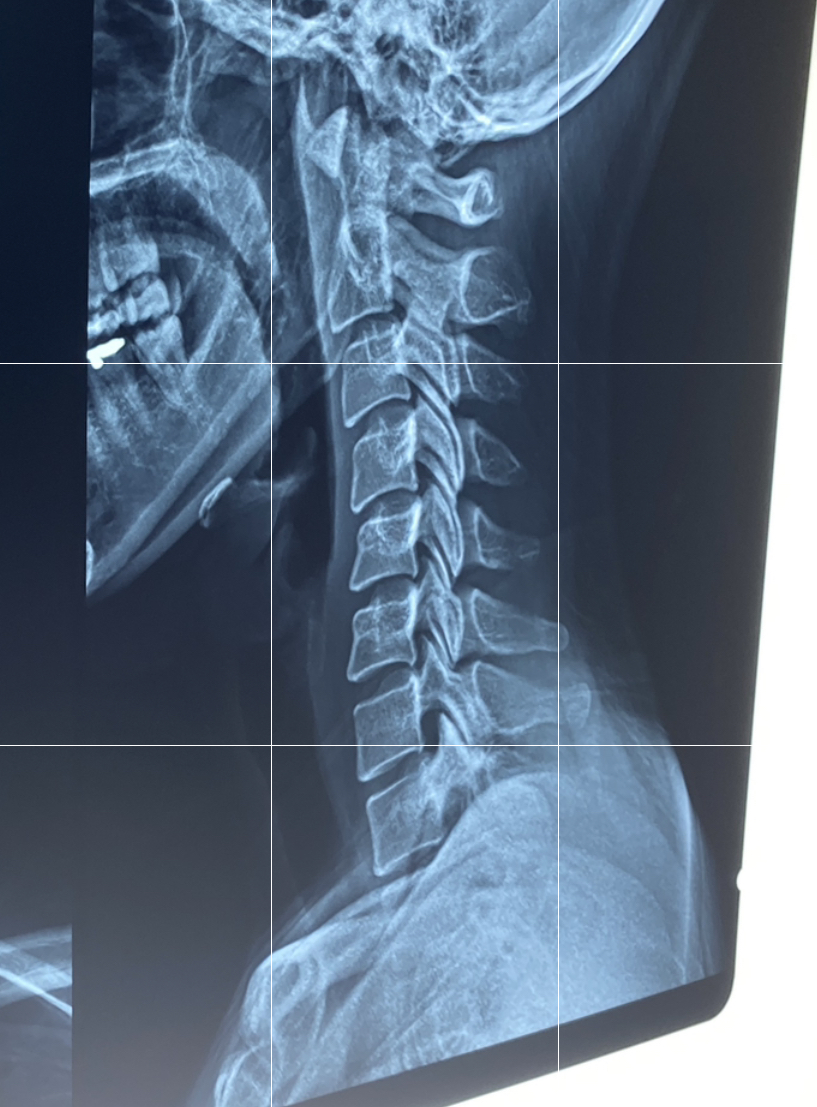

3층 방사선과(영상의학과)에서

목 쪽 엑스레이를 찍어오기로 한다

와 거북목 ㅋㅋㅋㅋ

6월 15일에는 바른자세로 억지로 쭉펴서 일자목 나왔는데

9월 15일에는 편하게 그냥 평소 생활하듯

굽은대로 찍었더니 거북목 나왔다 :))